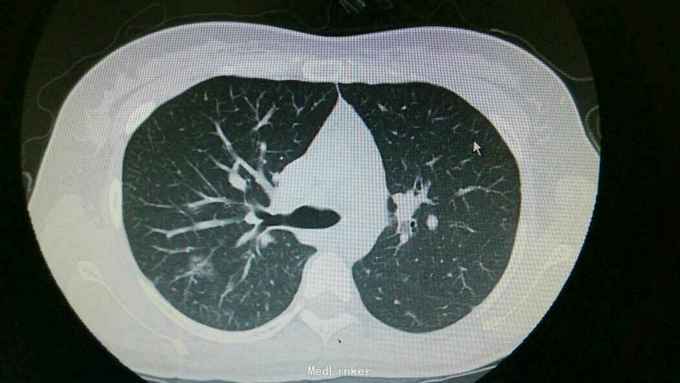

查体:双肺呼吸音粗,右肺可闻及湿罗音, 余无特殊 辅查:血常规示中性粒细胞稍高。胸片:右上肺野炎性病变。肺炎支原体抗体滴度1:640。胸部CT:双肺炎症。

诊断:支原体肺炎。 治疗,予以阿奇霉素抗感染,止咳化痰等处理。复查胸片提示炎症较前好转。

讨论+随访:临床支原体肺炎为不典型肺炎,其诊断主要依靠支原体抗体滴度及影像学检查。一般治疗一个星期可好转。